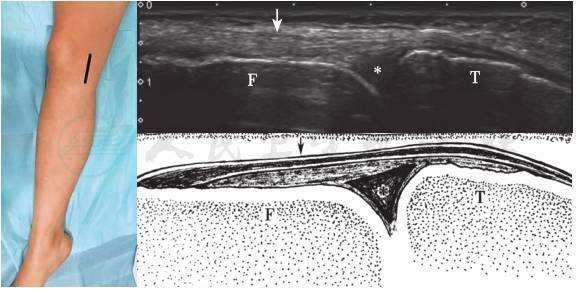

图7-15 膝内侧半月板声像图

F:股骨内上髁;T:胫骨内侧髁;*:内侧半月板

2.内侧半月板

内侧半月板位于股骨与胫骨之间,因其内为纤维软骨而在超声上呈高回声(图7-15)。超声检查时膝关节轻度外翻,可使关节间隙打开,从而能更好地显示内侧半月板。正常半月板呈高回声,纵切面上呈三角形,三角形的尖部朝向关节内;底部紧邻呈线状偏高回声的关节囊。显示内侧半月板体部后,将探头继续向前移动,以显示半月板前角。超声检查半月板时,还应注意其内有无异常回声。焦磷酸钙沉积病时,于半月板内可见强回声钙化沉积;痛风时,半月板内可见尿酸盐沉积呈强回声。